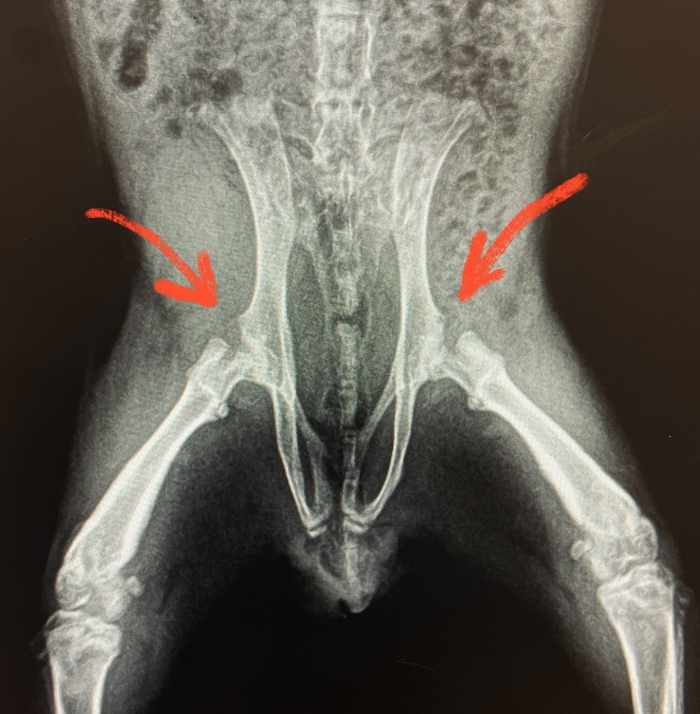

Морская свинка с тяжелой генетической болезнью суставов

Это чуть ли не один из моих первых пациентов с тяжёлым генетическим заболеванием

Пришли ко мне с маленькой морской свинкой с жалобой: «Задние ножки отказали внезапно»

Делаю снимки в разных проекциях. Смотрю внимательно позвоночник, сами лапки – нормально. И тут добираюсь до тазобедренных суставов. Реакция одна: ой ой ой… Даже не смотря на возраст, выглядит плохо.

Диагноз: Болезнь Пертесса

(вид остеохондропатии)

Если по-русски: разрушение головки бедренной кости.

Что именно я увидела на рентгене: головки бедренной кости нормально в ямке таза не стоят, все «погрызанные» кривые и шейки тонкие.

Выглядело это всё настолько плохо, что мы с хозяином сразу обговорили вариант ампутации обеих тазовых конечностей при отсутствии положительной динамики на лечение (это вместе с обсуждением случая со старшим коллегой хирургом). Конечно, хозяин расстроился. Но что уж поделать. Такой у него ребёнок.

На лечении свинка начала ходить. Но главным звеном в принятии окончательного решения был рентген. Потому что если по нему нет улучшений, то большая вероятность, что могут начать разрушаться кости таза. И то, что свинка ходит снова – вообще не на пользу.

Прошло три недели. Сделали повторный рентген.

На радость всем, по костям пошли маленькие, но улучшения. Ноги остаются при свинке)